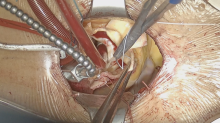

Aortic Root Exposition

In order to provide an excellent exposure, the aortic root is brought in a cephalad direction. This is achieved by putting the pledgeted 2-0 Ti-Cron horizontal mattress sutures above the commissures. These three commissural traction sutures are hitched up and snared in position. This simple manoeuvre provides an excellent exposure of the aortic valve for the minimal access surgical approach (the “Crane” manoeuvre).

Aortic Root Implantation

The aortic leaflets are resected, and the aortic annulus is decalcified. 2-0 Ti-cron annular sutures with or without pledgets are used. Horizontal mattress sutures are placed neatly below the aortic annulus. Pledgets are used to reduce the tension created by the sutures when the valve conduit is tied down, especially at the nadirs. The placement of these sub-annular sutures needs to be precise, both in terms of the spacing and whether the needle is passed through the annulus at a perpendicular angle. The sutures are evenly distributed.

The annulus is sized for its intra-annular and supra-annular dimensions. An appropriate valve conduit is selected. It is advisable not to oversize the valve. The annular sutures are passed through the sewing cuff of the prosthesis. Once all the sutures are passed through the sewing cuff, they are clipped and cut. The valve conduit is parachuted down by gently pulling the sutures vertically upwards with one hand and firmly pushing the valve conduit down onto the annulus with the other hand. Before tying each suture, it is important to check that there are no redundant loops of the sutures below the sewing cuff. The sutures are tied and cut one by one, starting from the three sutures at the nadirs of the annulus to ensure that the prosthesis is seated properly to the lowest points of the annulus. Then, the remaining sutures are tied and cut around the sewing cuff.

Coronary Button Re-implantation

The left coronary artery button is rested in its anatomical position. The appropriate site on the Valsalva graft (Vascutek Ltd, Renfrewshire, Scotland) for left coronary button re-implantation is determined. A Bovie electrocautery (Bovie Medical Corporation, Clearwater, FL, USA) is used to create a circular hole for receiving the left coronary button. The coronary button is trimmed, left with a 3 mm circumferential cuff and re-implanted using a 5-0 running polypropylene suture. The cuff of the coronary button needs to be attached snuggly to the outside of Valsalva graft.

In a similar fashion, the right coronary button is prepared and re-implanted. The appropriate site on the Valsalva graft for right coronary button re-implantation is determined with the heart fully loaded, so that there is no tension or rotation of the right coronary button anastomosis. Once the position of the anastomosis is marked, the heart is offloaded. It is imperative to ensure that a full thickness bite with each stitch is achieved. Systemic rewarming is subsequently initiated.